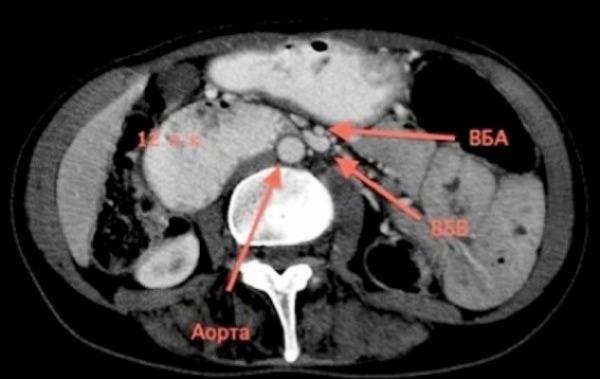

• КТ брюшной полости. Контраст пищеварительного канала с одновременной ангиографией брюшной части аорты назначают для проверки диагноза в сомнительных случаях. Исследование проводится для оценки стадии патологического процесса, измерения просвета двенадцатиперстной кишки, величины угла, по которому аорта и форма верхней брыжеечной артерии.

КТ брюшной полости. Артериомезентериальная компрессия.